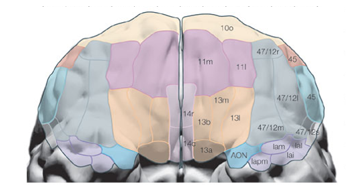

On retrouve une activation _______ du cortex orbitofrontal pour des renforçateurs abstraits

antérieure

On retrouve une activation _______ du cortex orbitofrontal pour des renforçateurs primaires

postérieure

On retrouve une activation _______ du cortex orbitofrontal pour des renforçateurs négatifs (punitions)

latérale

On retrouve une activation _______ du cortex orbitofrontal pour des renforçateurs positifs (récompenses)

médiane

La partie antérieure du cortex orbitofrontal répond à des renforçateurs _________

abstraits

La partie postérieure du cortex orbitofrontal répond à des renforçateurs _________

primaires

La partie latérale du cortex orbitofrontal répond à des renforçateurs _________

négatifs (punitions)

La partie médiane du cortex orbitofrontal répond à des renforçateurs _________

positifs (récompenses)